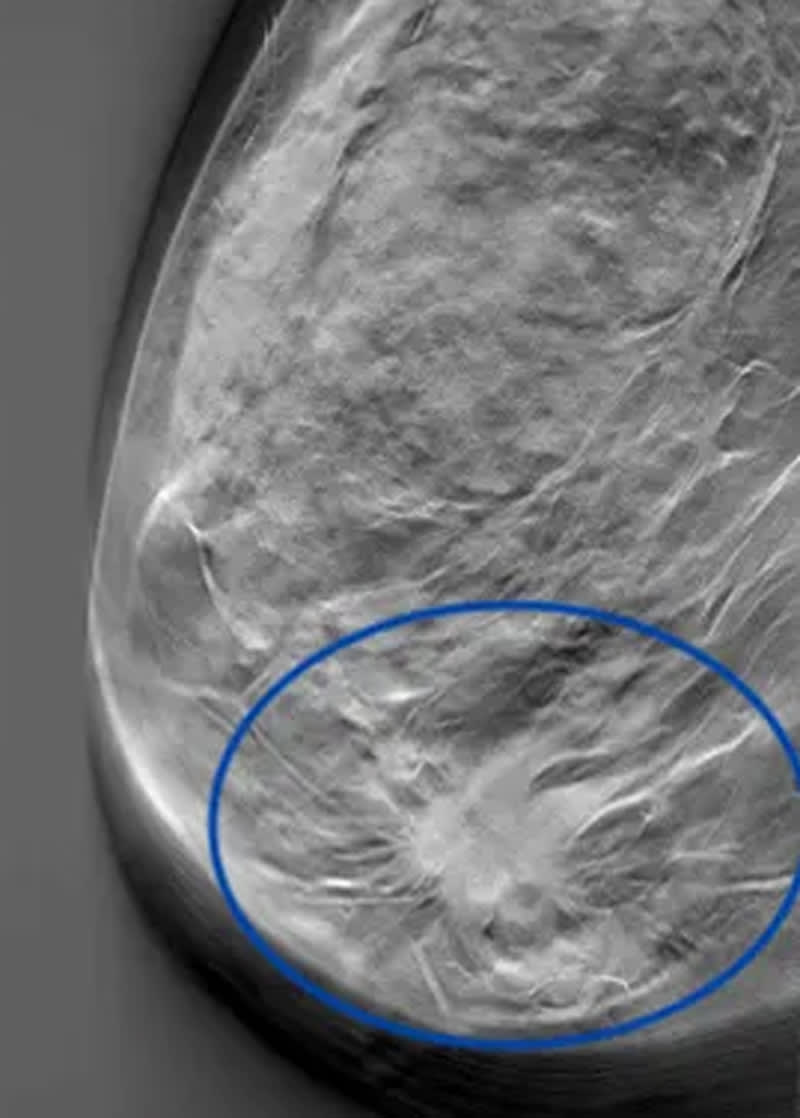

Oftast går det inte att se på ett bröst om det finns en cancertumör. Ibland kan man känna tumören, men i flesta fall upptäcks den via röntgen. Här är en 3D-bild från mammografi som visar en cancertumör i bröstet.

Mängden bröstkörtelvävnad i förhållande till fett avgör hur täta brösten är. Täta bröst gör det svårare att upptäcka eventuella tumörer med hjälp av mammografi. Körtelvävnaden ger samma vita färg på röntgenbilden som tumörer.

Fettvävnad ses som svarta områden på en mammografibild och gör att tumörer lättare kan upptäckas.